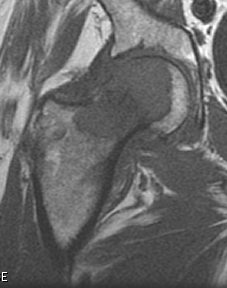

조골성 병변(Osteoblastic)이 관찰된다면 : 전립선암, 방광암, 자궁암 을 생각해 보아야 하며

혼합성 병변이 관찰된다면 : 유방암 을 생각해보아야 합니다.

전이성 골종양의 경우 영상과 같이 치료가 무척 어렵습니다. 지푸라기라도 잡는 마음으로 방사선치료와 항암화학요법을 할 수 있습니다. 5년 생존율이 높아 보이는 환자군에서 장관골과 골반골의 임박 골절, 병적 골절 에는 예방적 고정술을 해볼 수 있습니다. (RT에도 효과가 없고, 2.5cm 정도로 큰 사이즈와 cortex가 50%이상 파괴되어 부러지기 직전일때, 소전자의 견열골절이 있을때 = Mirel 8점이상)